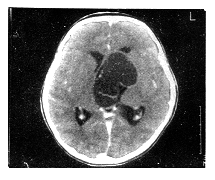

摘要 目的:研究治疗囊性颅咽管瘤最佳治疗方法。方法:对34例囊性颅咽管瘤进行CT立体定向囊腔内胶体磷酸铬内放疗。结果:全部病例经手术排除囊液后临床症状迅速改善,经囊腔内放疗后12~66个月随访,CT扫描显示28例(82.5%)瘤腔持续消失,3例(8.8%)瘤腔显著缩小,症状持续改善。3例(8.8%)分别于19、25、36个月后因瘤实质部分增大,症状恶化而相继死亡。无手术死亡率和严重并发症。结论:CT立体定向囊腔内放疗治疗囊性颅咽管瘤十分安全、有效,应作为治疗囊性颅咽管瘤首选的方法。

Abstract Objective: To investigate the value of sterotatic intracavitary irradiation for cystic craniopharyngiomas. Methods: Thirty-four patients with cystic craniopharyngiomas were treated with CT-guided stereotatic intracavitary irradiation with 32 P in a colloidal solution. Results: The clinical symptoms improved promptly after evacuations of cyst in all patients. No mortality or severe complications. Follow-up (ranged from 12 to 66 months) CT indicated the tumor cysts gradually regressed and disappeared in 28 cases (82.5%), decreased obviously in 3 cases (8.8%). However, other 3 patients died at the 19th, 25th and 36th month after operation because of the increasing solid parts of tumors. Conclusions: CT-guided stereotactic intracavitary irradiation for cystic craniopharyngioma is safe and effective, it should be the most appropriate initial surgical management.